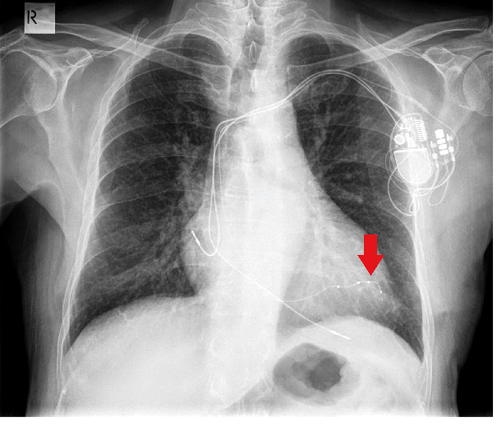

Where is the indicated pacemaker lead likely placed?

a) RV

b) LV

c) RA

d) Coronary sinus

A

Answer: Coronary Sinus

https://www.bjaed.org/article/S2058-5349%2817%2930025-2/fulltext similar to fig 1 -